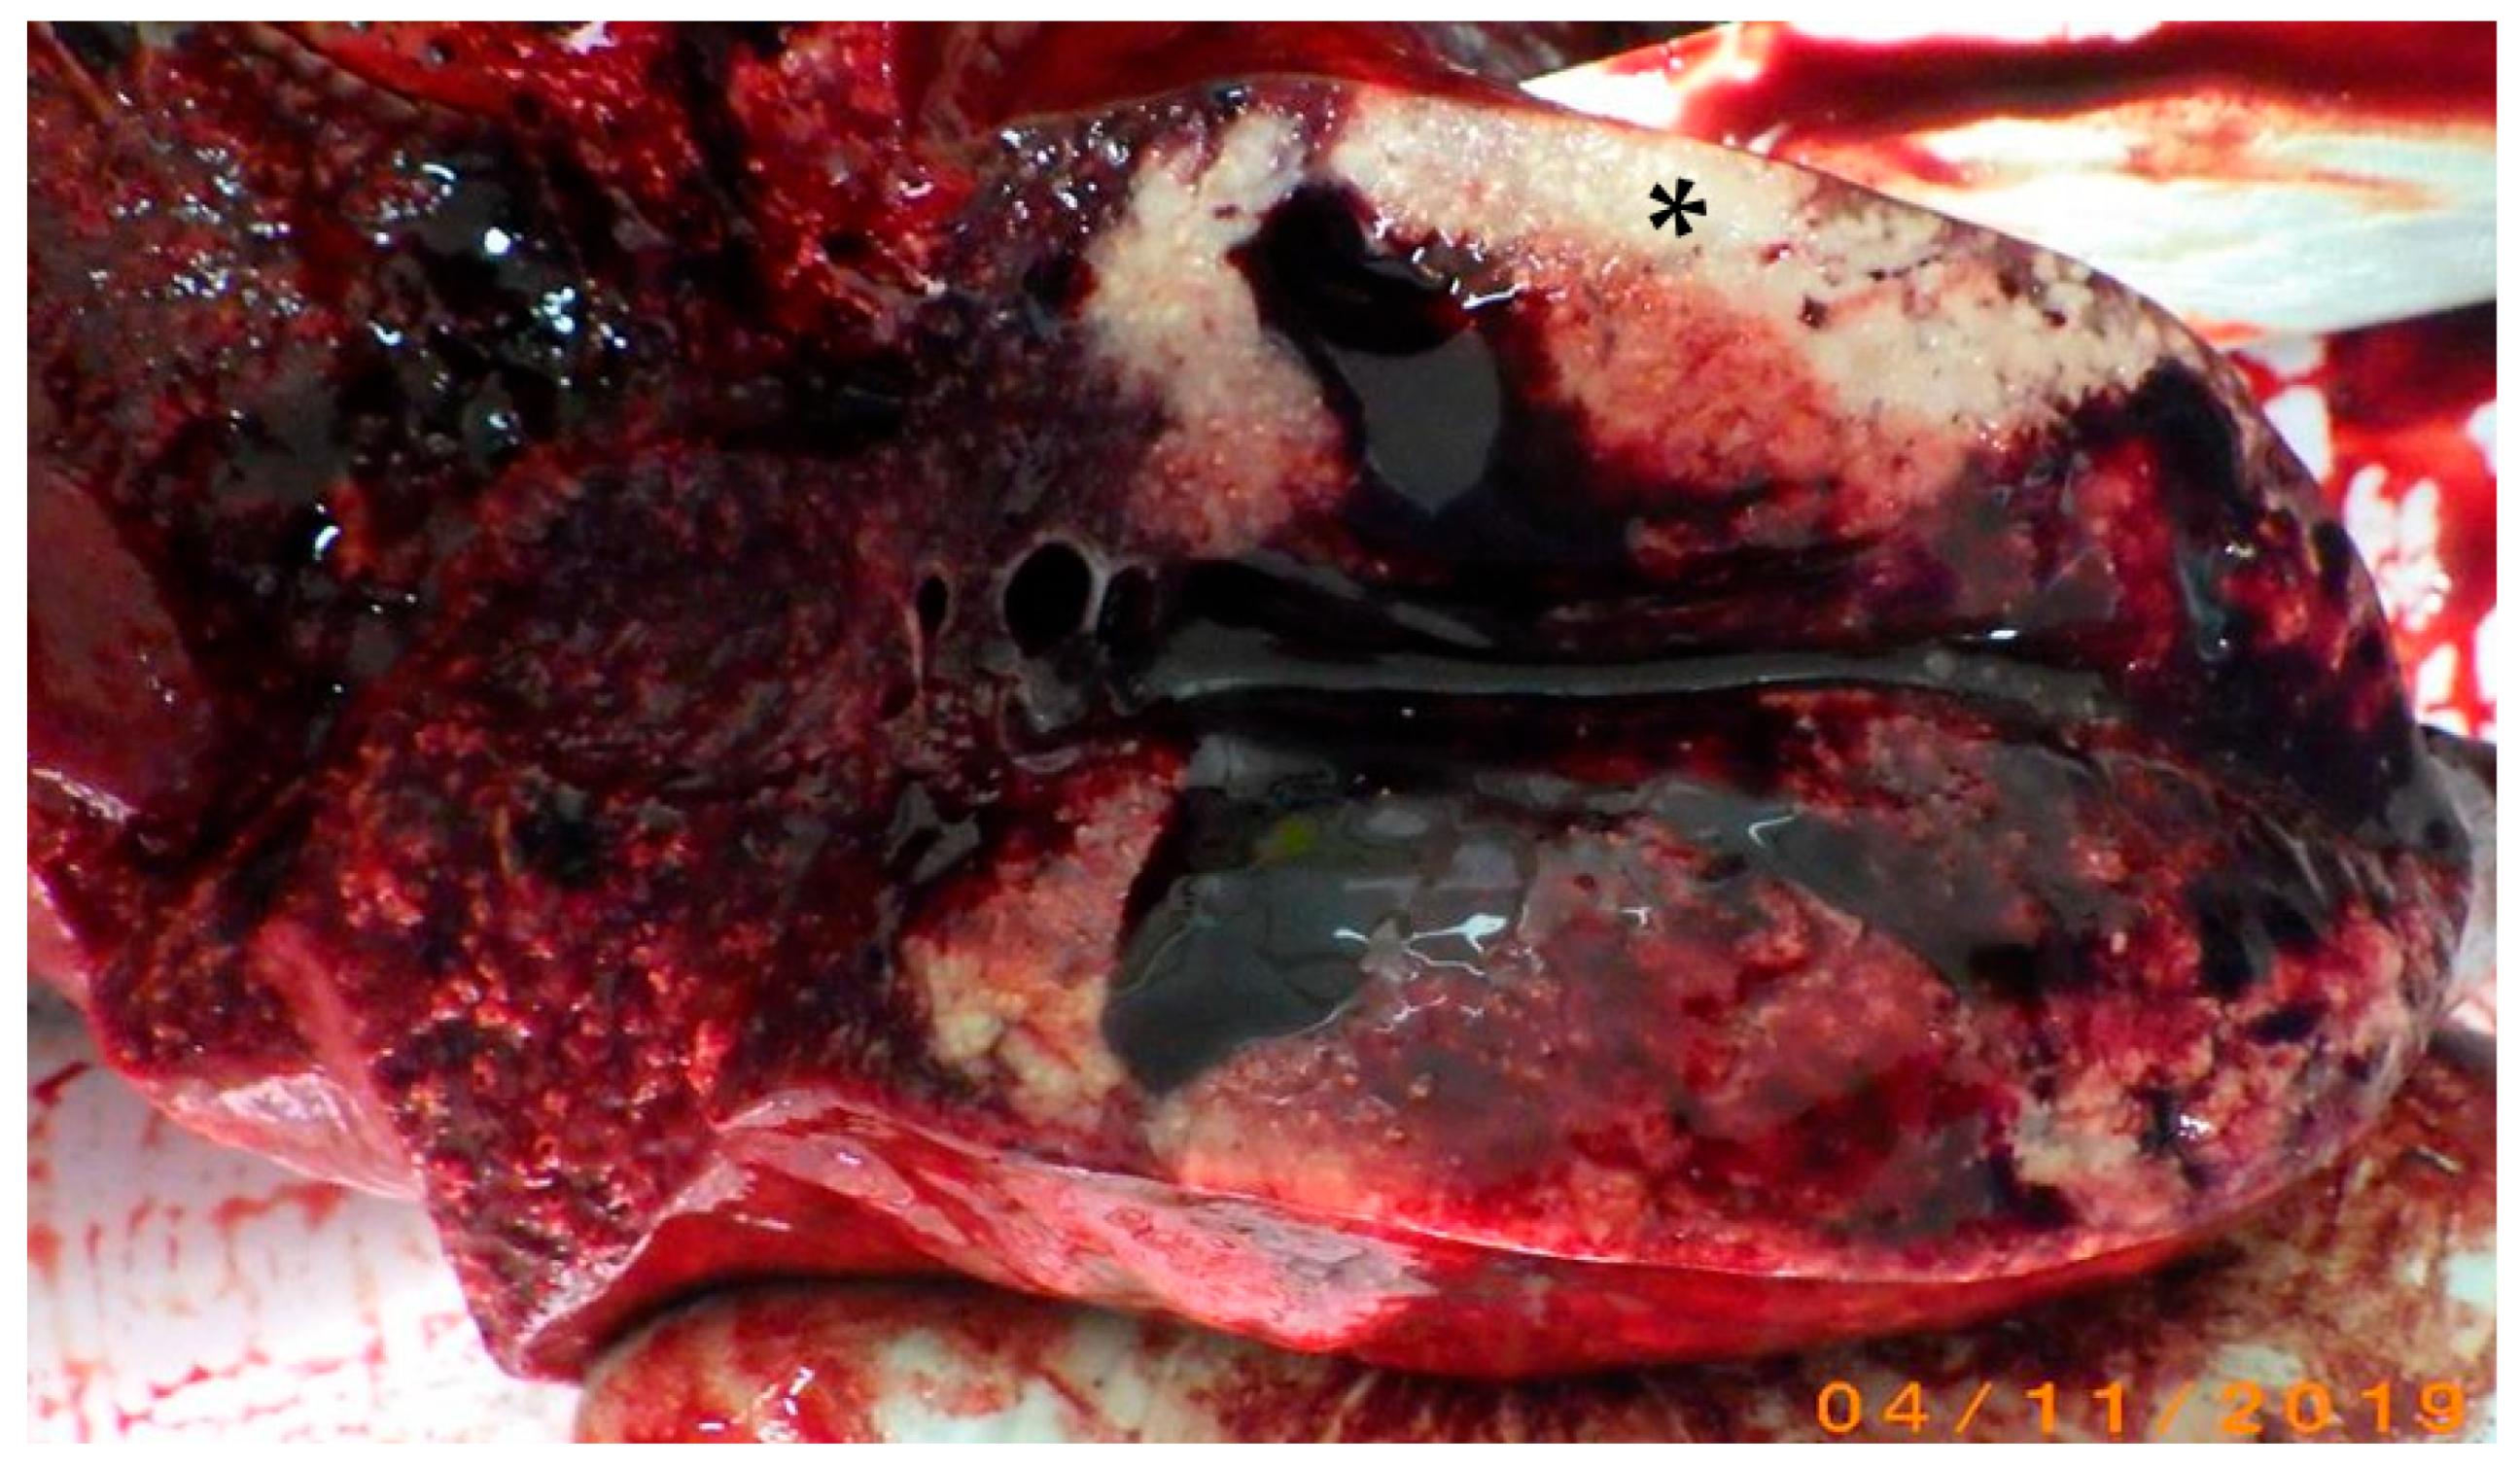

Bronchioloalveolar Carcinoma in a Striped Dolphin (Stenella coeruleoalba) Stranded on Thyrrhenian Sea Coast

3. Results